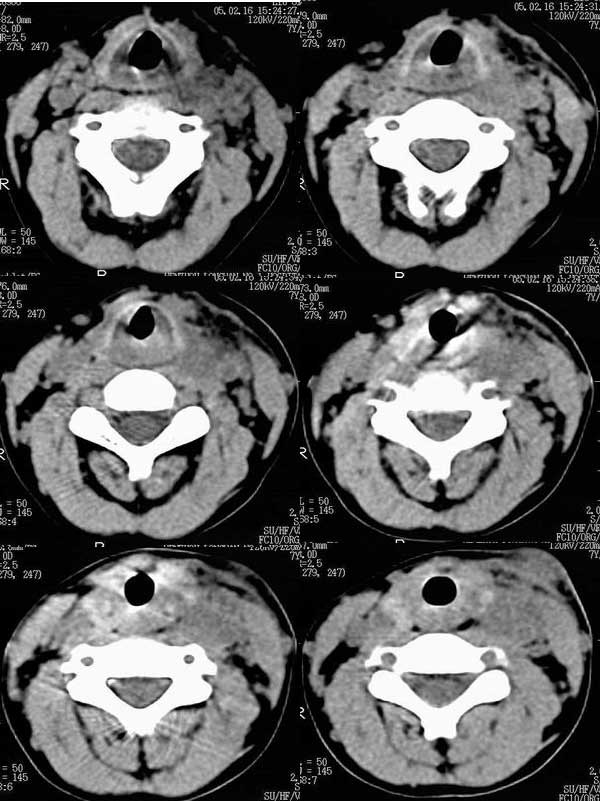

CT01020:[原创]左颈部肿块。

男孩7岁,左颈部肿块1个月,质软,有发烧病史。

是结核的可能的确很大。

首考虑感染性病变,以结核可能性大.

支持感染性病变。